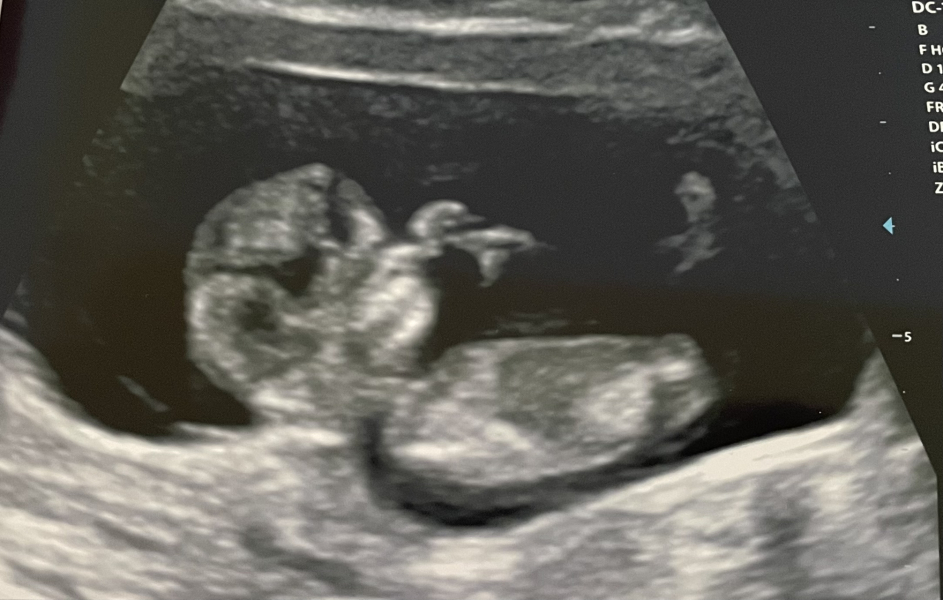

KittyFantastica · 04/08/2024 12:43

Hi all, how are you doing? I really hope you're all doing as well as can be.

Just going to leave this here as a little positive update. I'm still mostly keeping my head low and my heart hopeful.

We're 11 weeks today and we are measuring 11+4. Baby was moving around, stretching and sucking their thumb. It's the furthest we've ever got, and we were in floods of tears.

Keeping you all in my heart ❤️